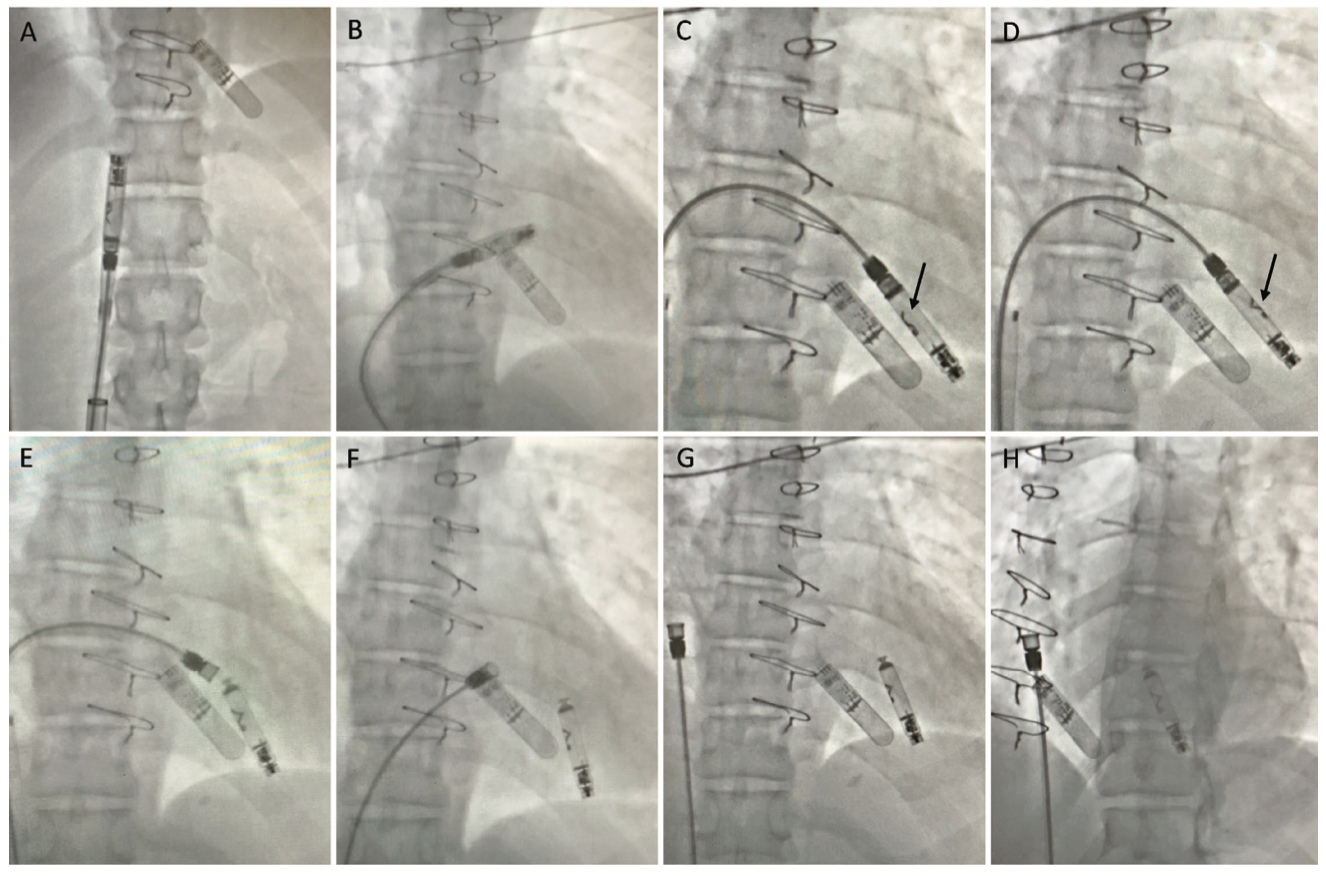

We present a case of a 39-year-old female with a past medical history of arrhythmogenic right ventricular cardiomyopathy, history of implantable cardioverter-defibrillator implantation with multiple shocks for ventricular tachycardia subsequent s/p OHT and subsequent redo OHT 14 years prior, who presented to the outpatient clinic for referral of presyncope. Of note, since transplant, the patient has done well from a heart failure standpoint. She is noted to be intolerant to tacrolimus with alopecia. She had a history of Class 1B rejection successfully treated with intravenous immunoglobulin, rituximab, and photopheresis twice (last treatment 6 years ago). She was recently noted to have Stage 4 chronic kidney disease (CKD) and underwent workup for renal transplant 1 year prior to presentation, but had subsequent improvement to Stage 2 CKD with plasmapheresis and medical management. The patient has remained very active in sports and shows adequate chronotropic competence. However, she was recently noted to have sporadic palpitations and presyncopal symptoms. An implantable loop recorder (ILR) was implanted and confirmed symptoms correlating with prolonged sinus pauses, with multiple pauses >10 seconds while awake and associated with near syncope (Figure 1). Given anticipated low pacing burden requirement, a desire to preserve venous vasculature given her young age, and recent renal dysfunction with concern for possible progression to renal failure, a shared decision to proceed with leadless pacemaker implantation was made. She underwent successful implantation of an active fixation Aveir leadless pacemaker (Abbott) in the right ventricle (RV) (Figure 2) as part of the LEADLESS II IDE trial. Device deployment was performed under fluoroscopic guidance (Figure 3). Acute implantation thresholds were noted to be 1.0V, sensed R-waves = 3 mV, impedance = 300 ohms with subsequent threshold increase to 2.25V approximately 10 minutes after deployment. Device was programmed to VVI 40 bpm, RV capture 5.0V @ 1.5 ms, 730 ohm impedance noted with 4.5 mV sensed R-wave. Successful hemostasis of the access site with figure-of-8 stitch and manual pressure was obtained.